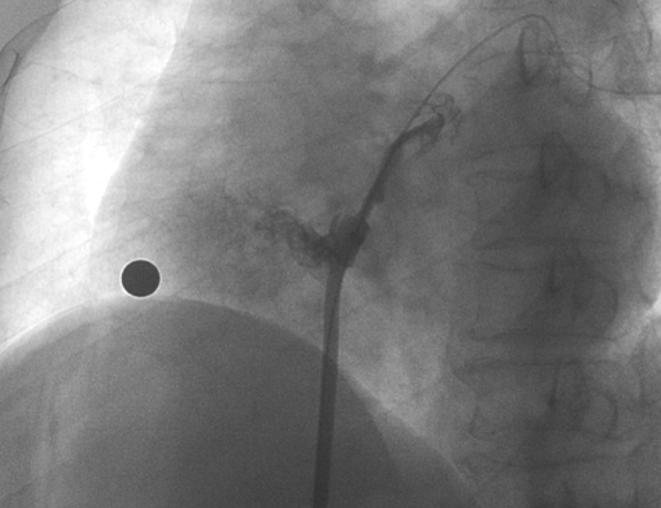

造影顯示長隧道型PFO

在本次植入手術中,接受介入封堵術的是一名卵圓孔未閉(長隧道型)的患者。患者60歲,男性,7年前曾診斷腦梗死,此次因新發腦梗死入院,無房顫及頸動脈狹窄;經胸心臟超聲和心臟聲學造影檢查提示卵圓孔未閉,Valsalva動作后心房水平大量右向左分流。經儲慧民教授團隊評估,結合相關病史并考慮PFO及不明原因卒中,遂決定對患者開展經皮PFO封堵術。

術中造影顯示患者為PFO且長隧道型,目前市場上已商業化的PFO封堵器難以滿足該患者解剖結構封堵需求。迪創醫療自主研發的OmniSeal PFO封堵器自適應性雙盤貼合設計能廣泛適應不同PFO隧道長度的解剖結構和形態,其雙盤外包覆式阻流和隧道內填充阻流相結合的雙重阻流設計,可為此患者實現有效封堵。與此同時,OmniSeal首創的完全可穿刺式設計,也為此患者最大程度地保留了房間隔區域穿刺通道,以實現全兼容未來可能的左心系統二次介入術。術終造影和心臟超聲顯示封堵完全、效果良好。作為OmniSeal的首例臨床應用,本次手術的順利完成和優異效果充分體現了產品的設計創新優勢。